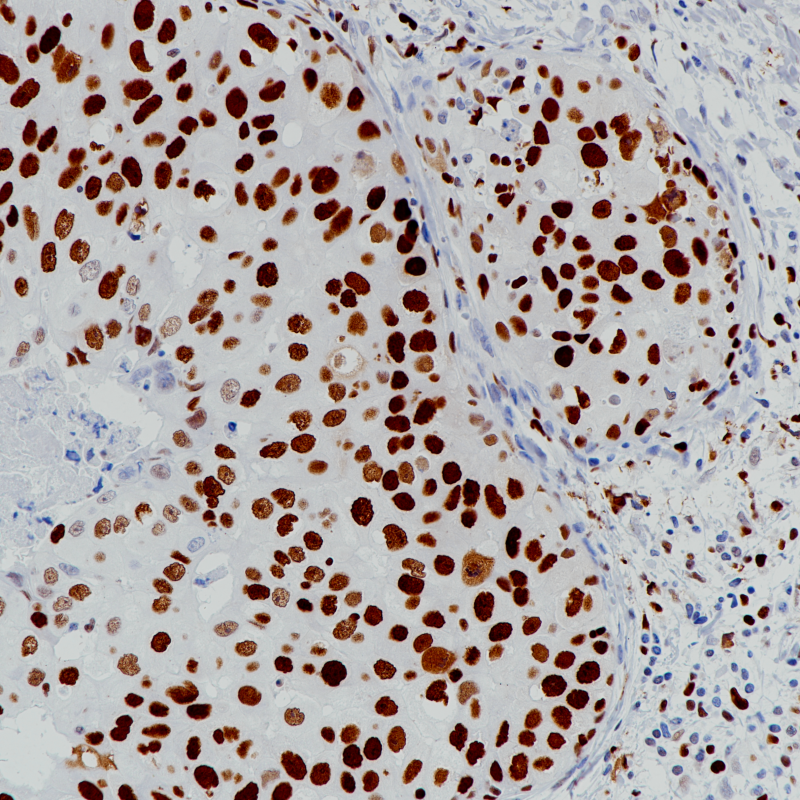

乳腺癌MCM2(BP6220)染色

MCM2作为MCM2-7复合体的组成部分,在耳蜗毛细胞的终分化发育中发挥作用,并诱导细胞凋亡。MCM2在所有增殖细胞中均有表达。作为一种特殊的细胞增殖标志物,在结肠癌、肺癌等上皮组织的癌前病变中优于Ki-67。它有助于恶性间皮瘤和反应性间皮瘤的研究。

乳腺癌

细胞核